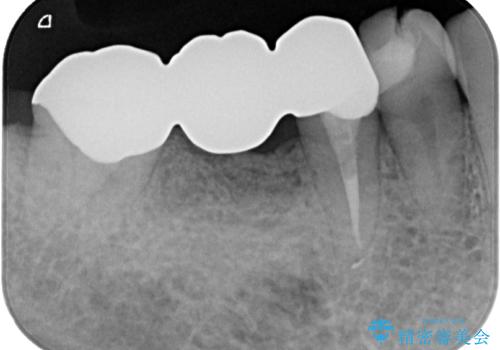

- 左下の4番目のセラミックの詰め物(セラミックインレー)が欠けたとのことで来院された患者様です。以前にセラミックの詰め物の治療を行い、噛み合わせが強く割れてしまっていました。今回はセラミックの詰め物のやり替えだとまた欠けてしまう可能性があるのでフルジルコニアクラウンでの治療を行うことにしました。拡大鏡視野下でセラミックの詰め物、虫歯を除去しフルジルコニアクラウンに適した形に整えました。

歯と歯茎の間に圧排糸と呼ばれる糸を入れてシリコーン印象を行いました。

見た目、機能面ともに満足していただけました。

噛み合わせが強い方なので今後はセラミックが割れないようにナイトガードを使っていただきながら、定期的にクリーニングで通ってもらう予定です。